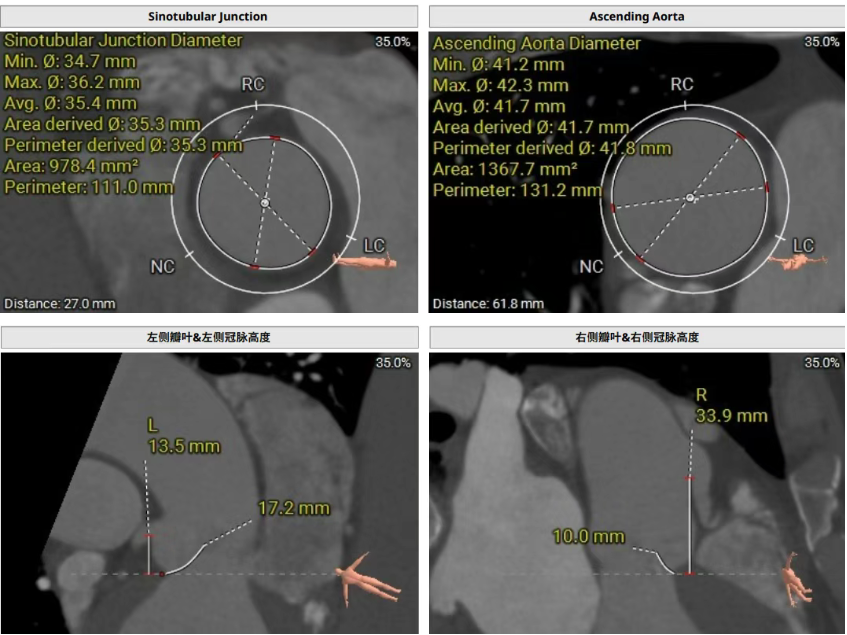

術前CT評估提示,患者主動脈瓣三葉瓣,瓣葉增厚,舒張期右冠瓣脫垂,右冠瓣瓣葉輕度鈣化,存在三個瓣竇,分布較均勻;主動脈瓣環周長折算直徑28.0mm;左心室流出道周長折算直徑29.5mm,無鈣化,無狹窄;STJ直徑35.3mm,升主動脈直徑41.8mm;雙側冠脈開口高度可LCA13.5mm ,瓣葉長17.2mm;RCA33.9mm,瓣葉長10.0mm;側左冠脈輕度鈣化;橫位心,左室主動脈夾角為135°;